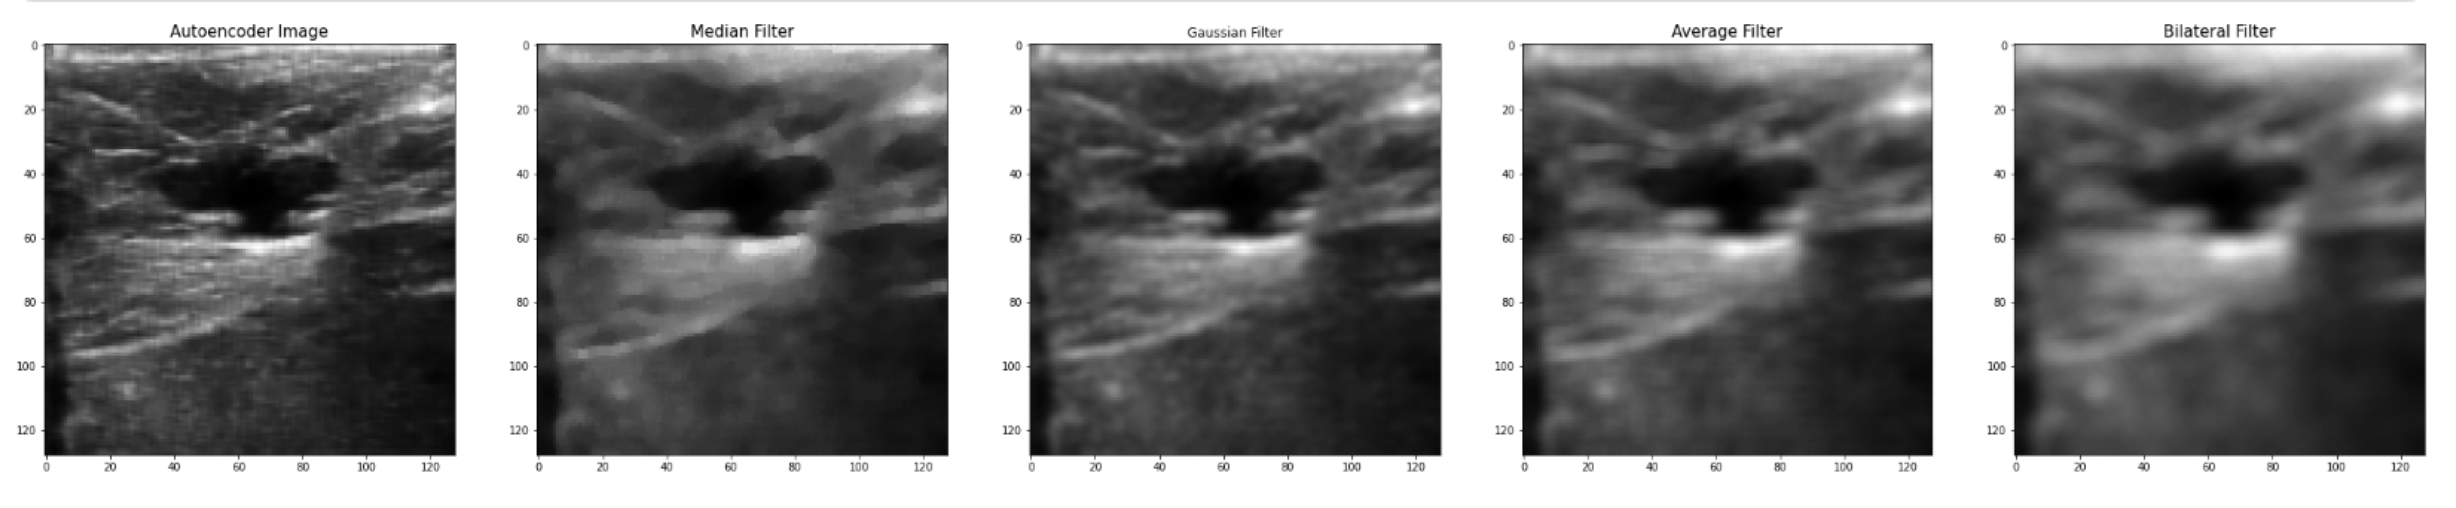

During the evaluation part, we compare the results of the CNN autoencoder with the old filter techniques. The first filtering technique is the Gaussian filter which is a low-pass filter that is used for noise reduction and adds blurring in regions in the image. The main parameter in this type of filtering is the standard deviation parameter. Increasing or a higher standard deviation the more effective in reducing the noise, but it may also lose small details in the image, which is one of the main limitations in previous papers. The second filtering technique is the Median filter, which is a non-linear filter, and it works by replacing each pixel value with the median value within a local neighborhood. It’s very effective in removing salt and pepper noise, it doesn’t lose important details, and it does not blur the image. The third filtering technique that we use to compare our results is the Average filter, and it works by replacing each pixel with the average value of its neighboring pixels. The last filtering technique is the Bilateral filter, which is a non-linear filter. It works by taking the weighted average neighbor pixels, and the weight depends on the distance between the pixel itself and the center pixel. It’s an effective way to remove noise while preserving the edges and small details.

The best PSNR results we have reached so far, as mentioned earlier is (PSNR = 30.44), while at the Median filter, it was (PSNR = 25.362), Gaussian filter (PSNR = 27.541), Average filter (PSNR = 24.934), and Bilateral Filter (PSNR = 23.675), as shown in details at table II, and we can conclude from these results that the CNN Autoencoder is better that the other filtering techniques by 20.02%, 10.52%, 22.08%, and 28.57%, respectively. These results came at an epoch size of 30, batch size of 16, and 256 filters in each of the CNN Layers using the combined dataset which consists of 1568 breast ultrasound images. Below is the training vs validation loss graph , as well as the output image compared to old filtering techniques.

While the best MSE results we have reached so far, is (MSE = 0.0009), while at the Median filter, it was (MSE = 0.0022), Gaussian filter (MSE = 0.0017), Average filter (MSE = 0.0028), and Bilateral Filter (MSE = 0.0034) and we can conclude from these results that the CNN Autoencoder is better than the other filtering techniques. These results came at an epoch size of 50, batch size of 16, and 256 filters in each of the CNN Layers using the combined dataset which consists of 1280 breast ultrasound images, also the same MSE came at an epoch size of 30, batch size 16, and 256 filters in each of the CNN Layers, and a dataset of size 1568 ultrasound images.

The best SSIM results we have reached so far is (SSIM = 93.5%) while at Median filter it was (SSIM = 78.5%), Gaussian filter (SSIM = 87.1%), Average filter (SSIM = 76.9%), and Bilateral Filter (SSIM = 70.7%) and we can conclude from these results that the CNN Autoencoder is better than the other filtering techniques. These results came at an epoch size of 30, batch size of 16, and 256 filters in each of the CNN Layers using the combined dataset which consists of 1568 breast ultrasound images.